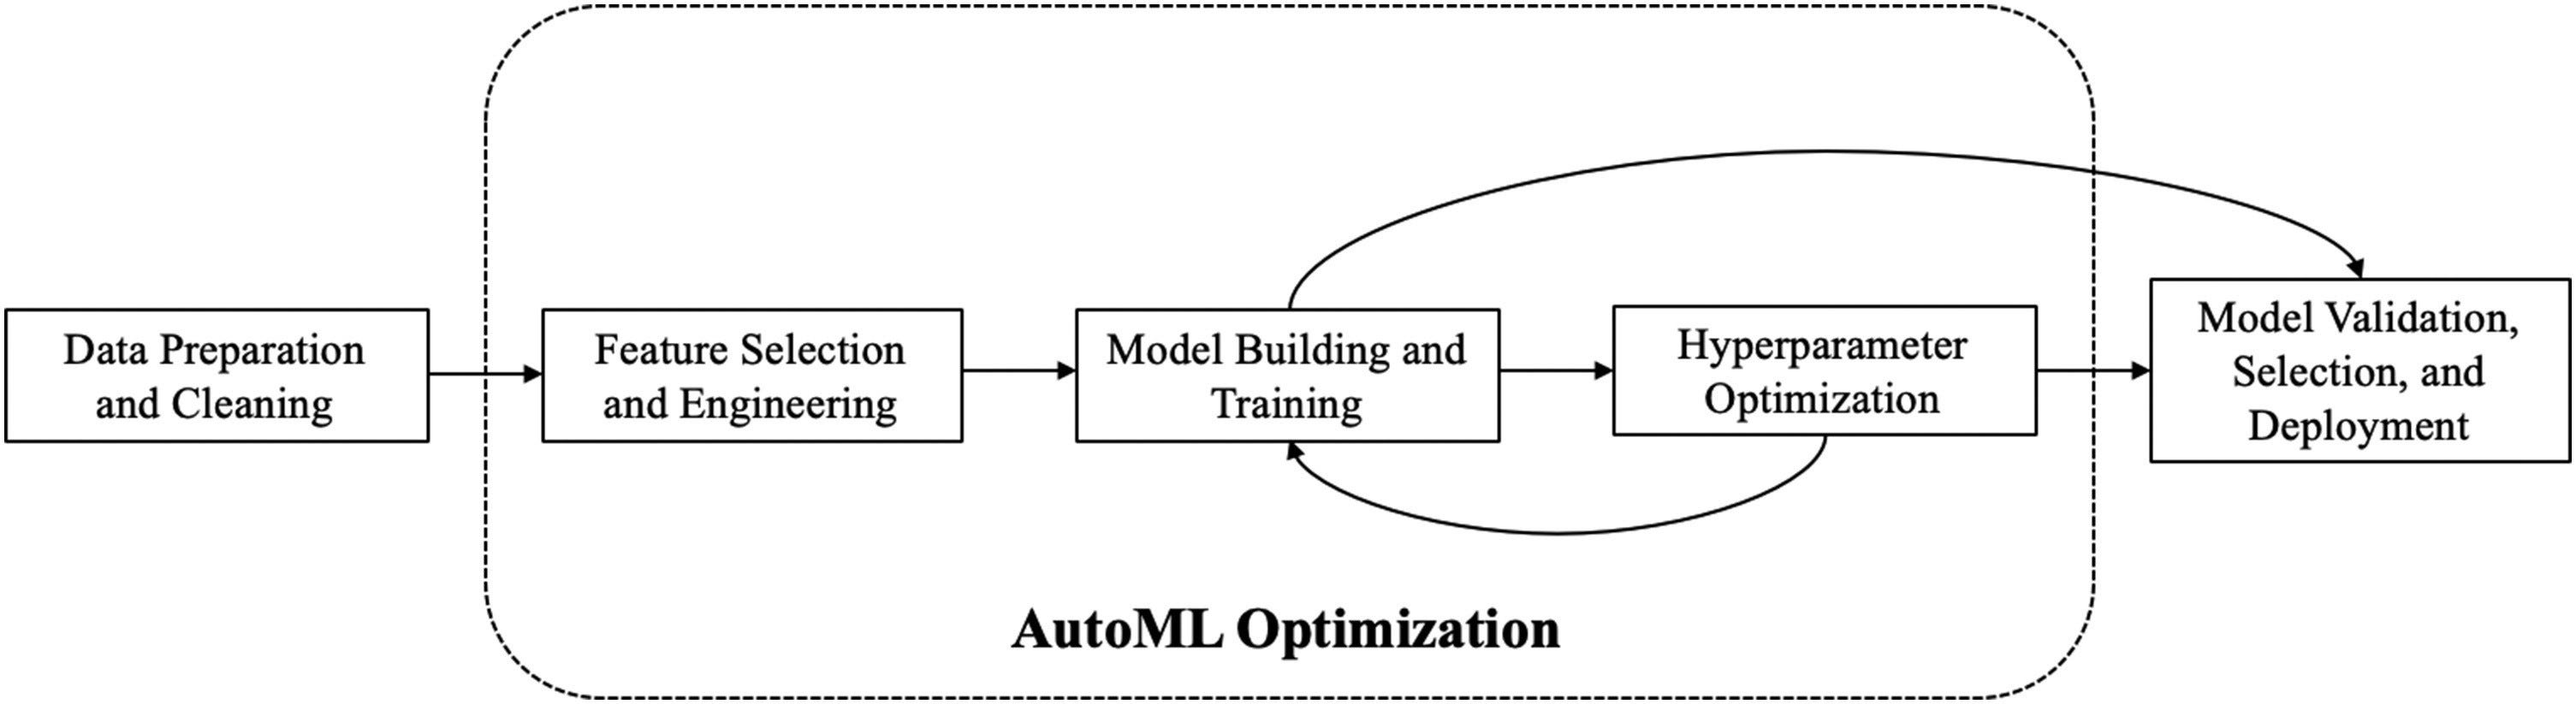

Above figure depicts the typical components of machine learning cycle. It starts with data preparation and cleaning and applying transformations, normalizations or encoding, which is extremely critical for the performance of machine learning models. The next step involves selecting the right set of features to avoid overfitting or underfitting of the machine learning models. It can also include feature engineering, which leverage domain knowledge to create new features for improvising the machine learning models. The subsequent stages involves building machine learning models, training, optimizing, validating and selecting machine learning models to solve a problem (Waring et al., 2020).

上图描绘了机器学习周期的典型组成部分。 它从数据准备和清理以及应用转换,规范化或编码开始,这对于机器学习模型的性能至关重要。 下一步涉及选择正确的功能集,以避免过度拟合或不足拟合机器学习模型。 它还可以包括特征工程,该特征工程利用领域知识来创建用于改进机器学习模型的新特征。 随后的阶段包括建立机器学习模型,训练,优化,验证和选择机器学习模型以解决问题(Waring等人,2020年)。